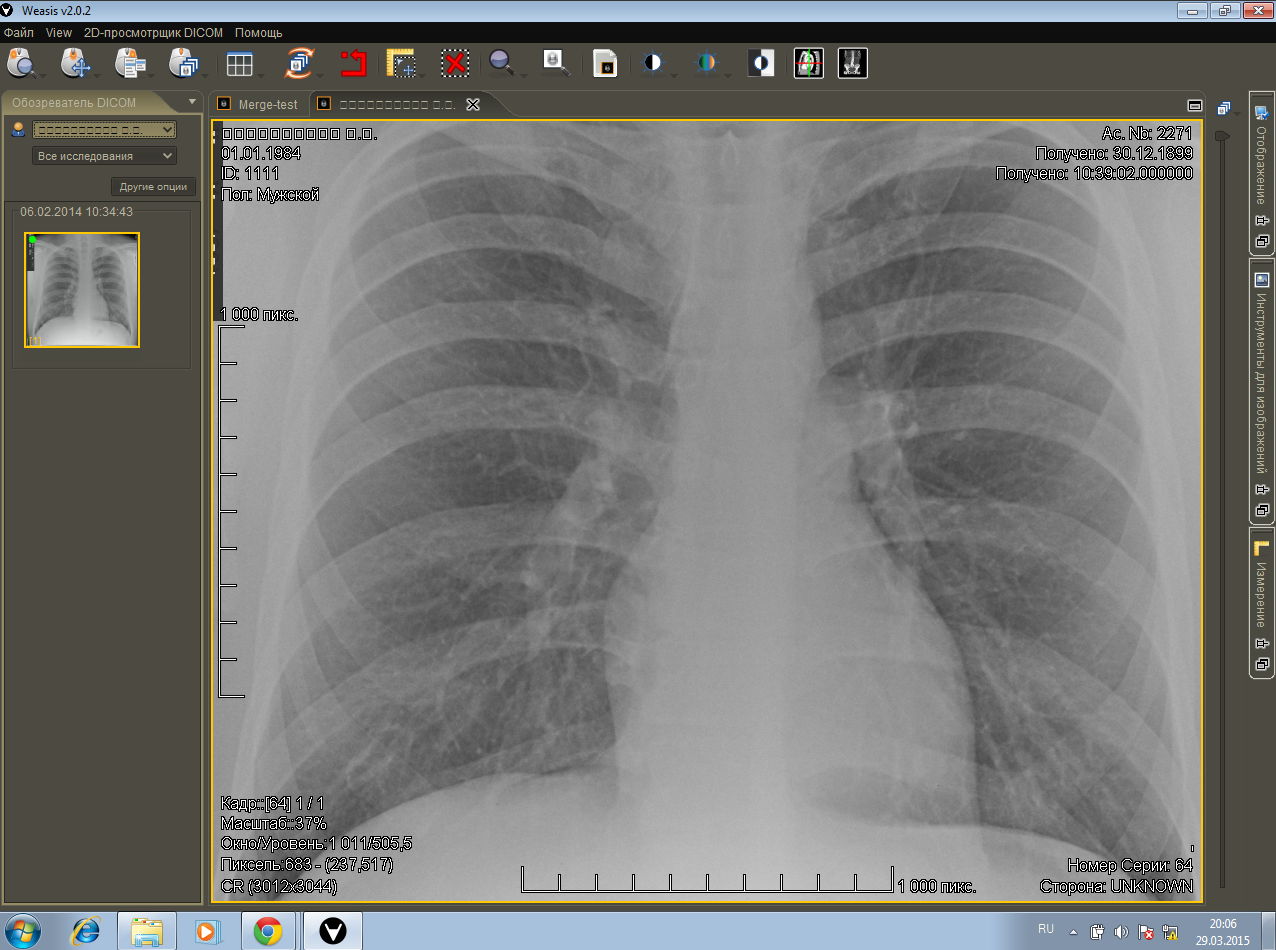

Просмотр изображений в weasis: